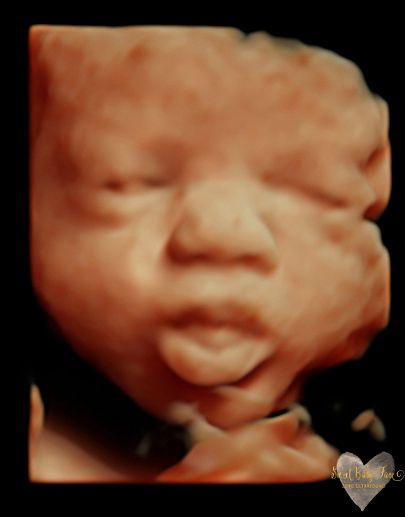

3D/4D/5D Ultrasound Gallery

Take a peek at our Photo Gallery. All of our 2D, 3D, 4D, HD elective ultrasound images are truly ours. They come directly off our machine from our highly trained staff. We can start getting great 3D/4D images as early as 10 weeks!